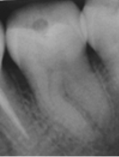

En 2011 concurre paciente de sexo masculino, de 22 años, por caries profunda en pieza 38. Radiográficamente se destaca la cercanía de la cavidad cariosa con respecto a la amplia cámara pulpar (Fig. 3a). Se diagnostica CPPA, luego de eliminar la dentina necrótica reblandecida superficial con cucharita de dentina y verificar su vitalidad con test de fresado. En la evaluación dentinaria se constata dentina de color marrón, blanda y húmeda. Se planifica Técnica de eliminación de caries en etapas. La Fig.3b muestra eliminación total de caries de paredes laterales con control colorimétrico sin tocar la pared pulpar.